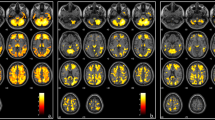

Correlation study between R2* values of different regions of the brain in patients with SCD and the studied neurocognitive parameters showed no significant correlation except positive correlation between left caudate R2* and anxiety value (r = 0.724, p = 0.012). There were positive correlation between hemoglobin S% and both left caudate R2* (r = 0.015, p = 0.031) and right thalamus R2* (r = 0.612, p = 0.105) and a negative correlation between hemoglobin A% and left caudate R2* (r = −0.568, p = 0.027). There were positive correlation between left caudate R2* and age and negative correlation between transfusion index and right thalamus R2* as shown in Fig. 1. However, there was non-significant correlation between mean pre-transfusion hemoglobin and the R2* values of different regions of the brain.

A seventeen-year-old female patient with SCD, on regular blood transfusion, had serum ferritin level equal 7426 ng/mL. Her liver iron content equals 7.49 mg/g, cardiac T2* equals 41 ms, cardiac R2* equals 24.4 Hz, and her calculated MIC equal 0.48 mg/g. Figure 2 showed that her estimated left thalamus T2* was 69.1 ms, R2* 14.5 Hz, and calculated left thalamus R2* was 14.5 Hz (within the normal range of R2* of healthy controls (13.3–16.9)).

Multi-echo fast gradient echo brain MRI T2* sequence. Left: region of interest is drawn at the left thalamus (highlighted in red) for measuring the mean signal intensity throughout multiple echo times to calculate the R2*. Right: data analysis using Microsoft Excel spreadsheet V 2.01: the signal intensity (TE) is plotted against multiple TE values. The exponential signal decay curve is then constructed. T2* and R2* values are calculated automatically in the left thalamic region